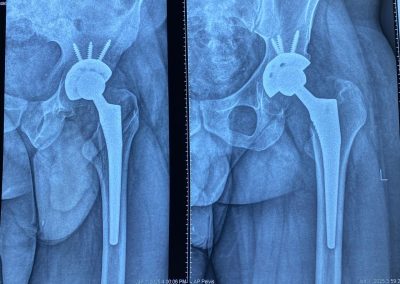

حسام الدين عبدالجليل

٣٠ عاما

يعاني من تاكل شديد منذ الطفولة في مفصل الحوض الأيسر.